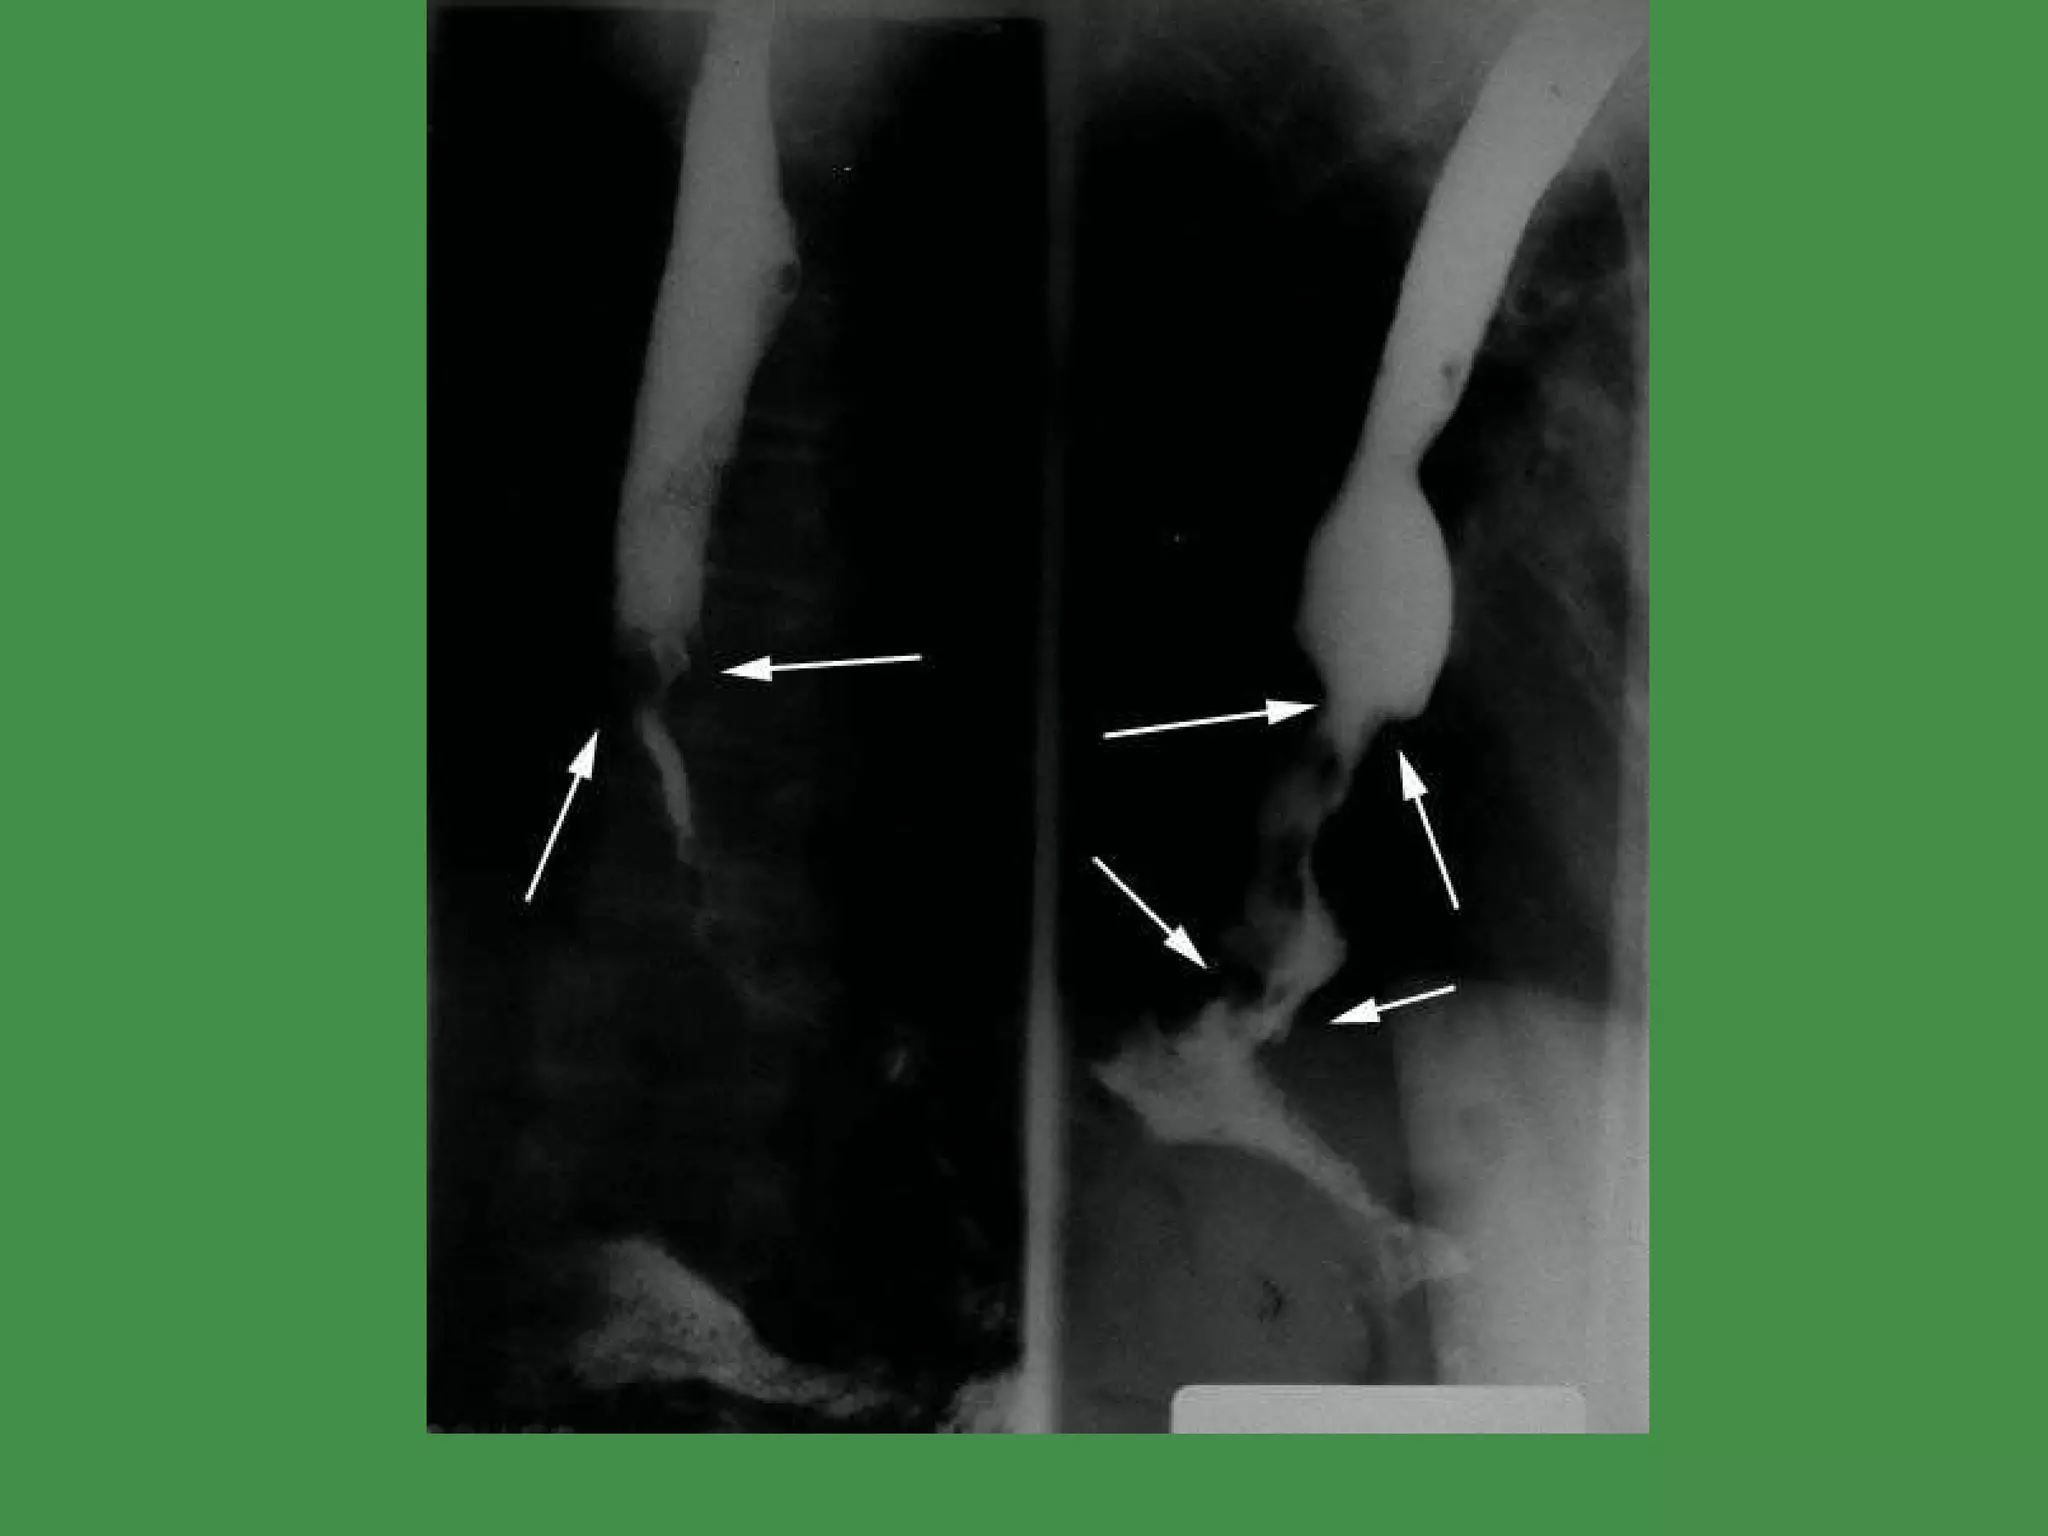

HIATAL HERNIA Diaphragmatic muscular defect WIDENING of the space which the lower esophagus passes through IN ALL cases, STOMACH above diaphragm Usually associated with reflux Very common   Increases with age Ulceration, bleeding, perforation, strangulation www.freelivedoctor.com

DIVERTICULA ZENKER (HIGH) ‏ TRACTION (MID) ‏ EPIPHRENIC (LOW) ‏ TRUE vs. FALSE? www.freelivedoctor.com

HIATAL HERNIA Diaphragmaticmuscular defect WIDENING of the space which the lower esophagus passes through IN ALL cases, STOMACH above diaphragm Usually associated with reflux Very common  Increases with age Ulceration, bleeding, perforation, strangulation www.freelivedoctor.com

DIVERTICULA ZENKER (HIGH)‏ TRACTION (MID) ‏ EPIPHRENIC (LOW) ‏ TRUE vs. FALSE? www.freelivedoctor.com

• #14 Hiatal hernia with SHATZKI ring.

• #15 “ TRUE” diverticula usually have all 4 layers in its wall: Muc/Submuc/Musc/Adventitia. Which one of these might result in dysphagia? Ans: Zenkers